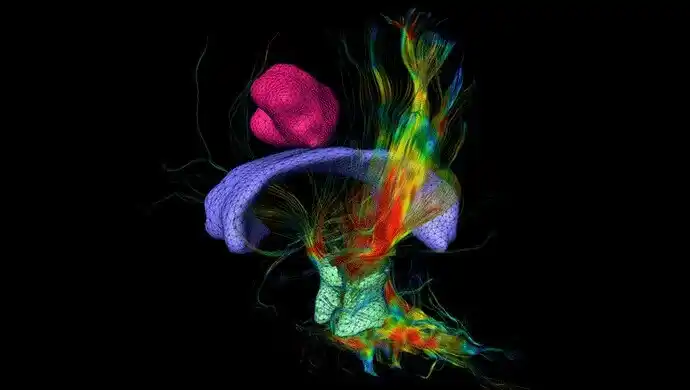

XNeuro – Diffusion Tensor Imaging and perfusion analysis

Amira Software solution to perform water diffusion analysis using diffusion weighted MRI. It enables the user to compute the apparent diffusion coefficient, fractional anisotropy, and directionally encoded color maps. Diffusion tensor imaging aims at localizing and visualizing fiber tracts. Full brain perfusion analysis can be performed on dynamic contrast enhanced MRI or CT studies. Learn more